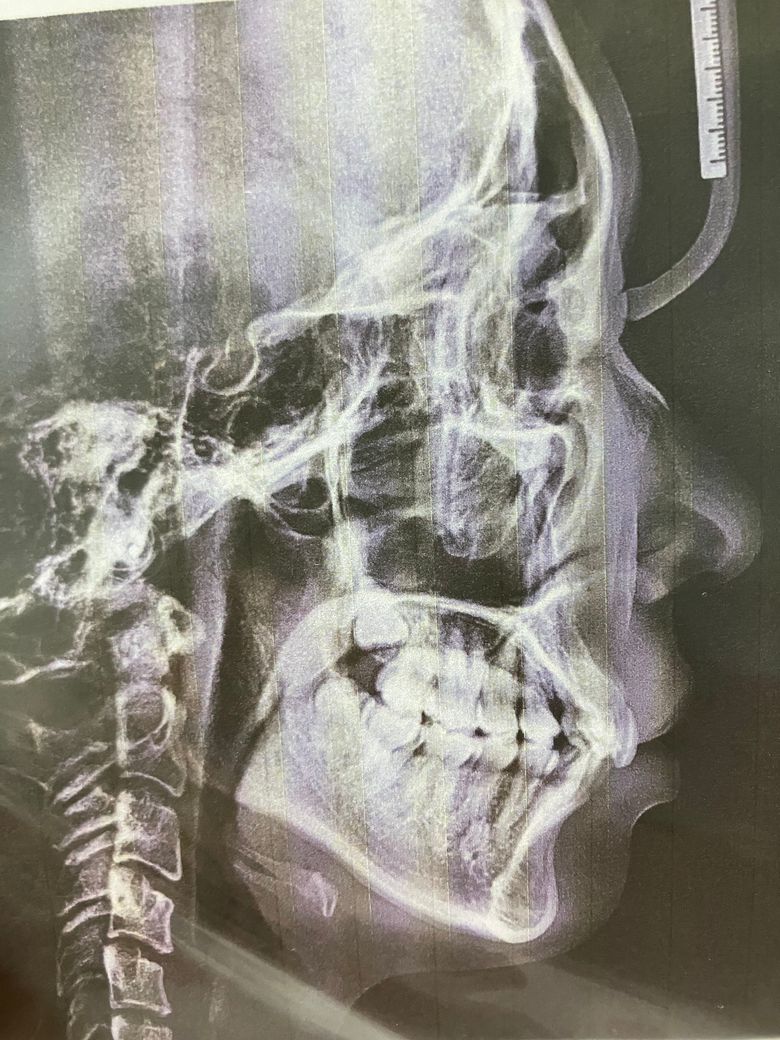

만약 교정을 하게 되면 이 상태에선 앞니를 들어올리나요? 아니면 어금니를 조정하나요?

이갈이나 이 악무는 습관은 없습니다. 이 상태로면 교정 없이도 노인이 될 때까지 괜찮을까요?

나이가 들 수록 더 깊어져서 아랫니가 윗니를 치고 입천장을 친다는데.. 그렇게 될까요? 현재는 위아래 앞니가 막 닿진 않고 고개를 숙이거나 움직일 때 종종 살짝 닿아요..이건 정상인가요?

• 2번 째 사진

어금니 맞물림은 거의 정상에 가깝고, 위아래 앞니 과개교합이 다소 있습니다. 보통 1/4정도 위 아래 앞니가 아래 앞니를 덮는 것이 정상이나 지금보면 1/2이상 덮고 있습니다. 마모가 점차 심해지면 과개교합도 계속 심해집니다. 교정치료계획은 지금 이 자료만으로는 어떻게 진행된다 단정하기 어렵습니다.

과개교합이 심하지 않고 일상 생활에 큰 불편함이 없다면 교정이 필요하지 않을 수도 있습니다.

과개교합이 있으면 시간이 지나면서 입을 닫을 때 턱에 과도한 압박이 가해지거나, 치아가 점차적으로 비정상적으로 마모되거나 이동할 수 있습니다. 이로 인해 턱관절에 문제가 생기거나 치아의 배열이 더욱 나빠질 수 있습니다.

따라서 교정치과에 방문하여 현재 교합을 정밀하게 검사 및 진료를 받아보고 교정여부를 결정하길 권합니다.